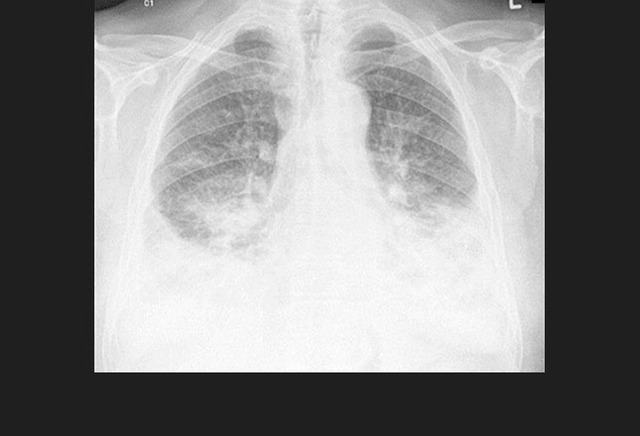

图5. 一位HIV阳性患者的继发性肺结核

HIV改变了结核的发病机制,因此极大的增加了结核进展的风险,导致更容易出现肺外侵犯,出现不典型的X-线表现。

整体而言,结核是HIV血清学阳性患者最常见的机会性感染,也是AIDS患者最常见的死亡原因。